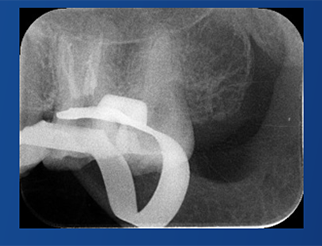

C-Root SP是預(yù)混合的、可即刻應(yīng)用的、可注射的、遇水凝固的硅酸鹽類生物活性陶瓷糊劑材料,主要成分為硅酸鍶、氧化鋯、磷酸鈣、氫氧化鈣,用于根管的密封和永久充填,適合單尖法、側(cè)壓法和熱牙膠法。 C-Root SP為世界口腔醫(yī)生提供一個“鍶生物陶瓷”的新選擇! >>>

祝自洋老師案例